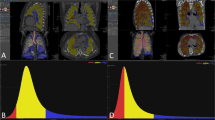

The Gaussian histogram normalized correlation (GHNC) method classifies pixels in a target image into different categories. In the GHNC method, a set of Gaussian histograms of CT attenuation values of the original image and the differential image are extracted from samples of each category in advance. The normalized correlations between the Gaussian histograms in the surrounding local 50-pixel area of a pixel and those of the categories are then compared for classification into the predefined categories. To avoid the effects of random noise, pixel attenuation is assumed to have random noise with a Gaussian distribution. Gaussian convolution filtering is applied to the extracted histograms from the local area and the samples in the categories.

The Gaussian histogram of the predesigned sample is obtained from the following formula:

in which α is the Hounsfield units of each pixel and N α is the number of pixels in the predesigned sample area D α. The variable σ is the standard deviation of the Gaussian random noise.

The Gaussian histogram of the target area D β is given by

in which β and N β also denote the Hounsfield units and the number of pixels in the target area D β, respectively.

The normalized correlation between α g(x) and β g(x) is given by the formula

In our method, the normalized correlations are calculated in the local area of each target pixel for the original and differential images. The product of both correlations is then used as the similarity of the target and the predesigned sample pattern in each category to classify the target pixels into the predesigned categories.